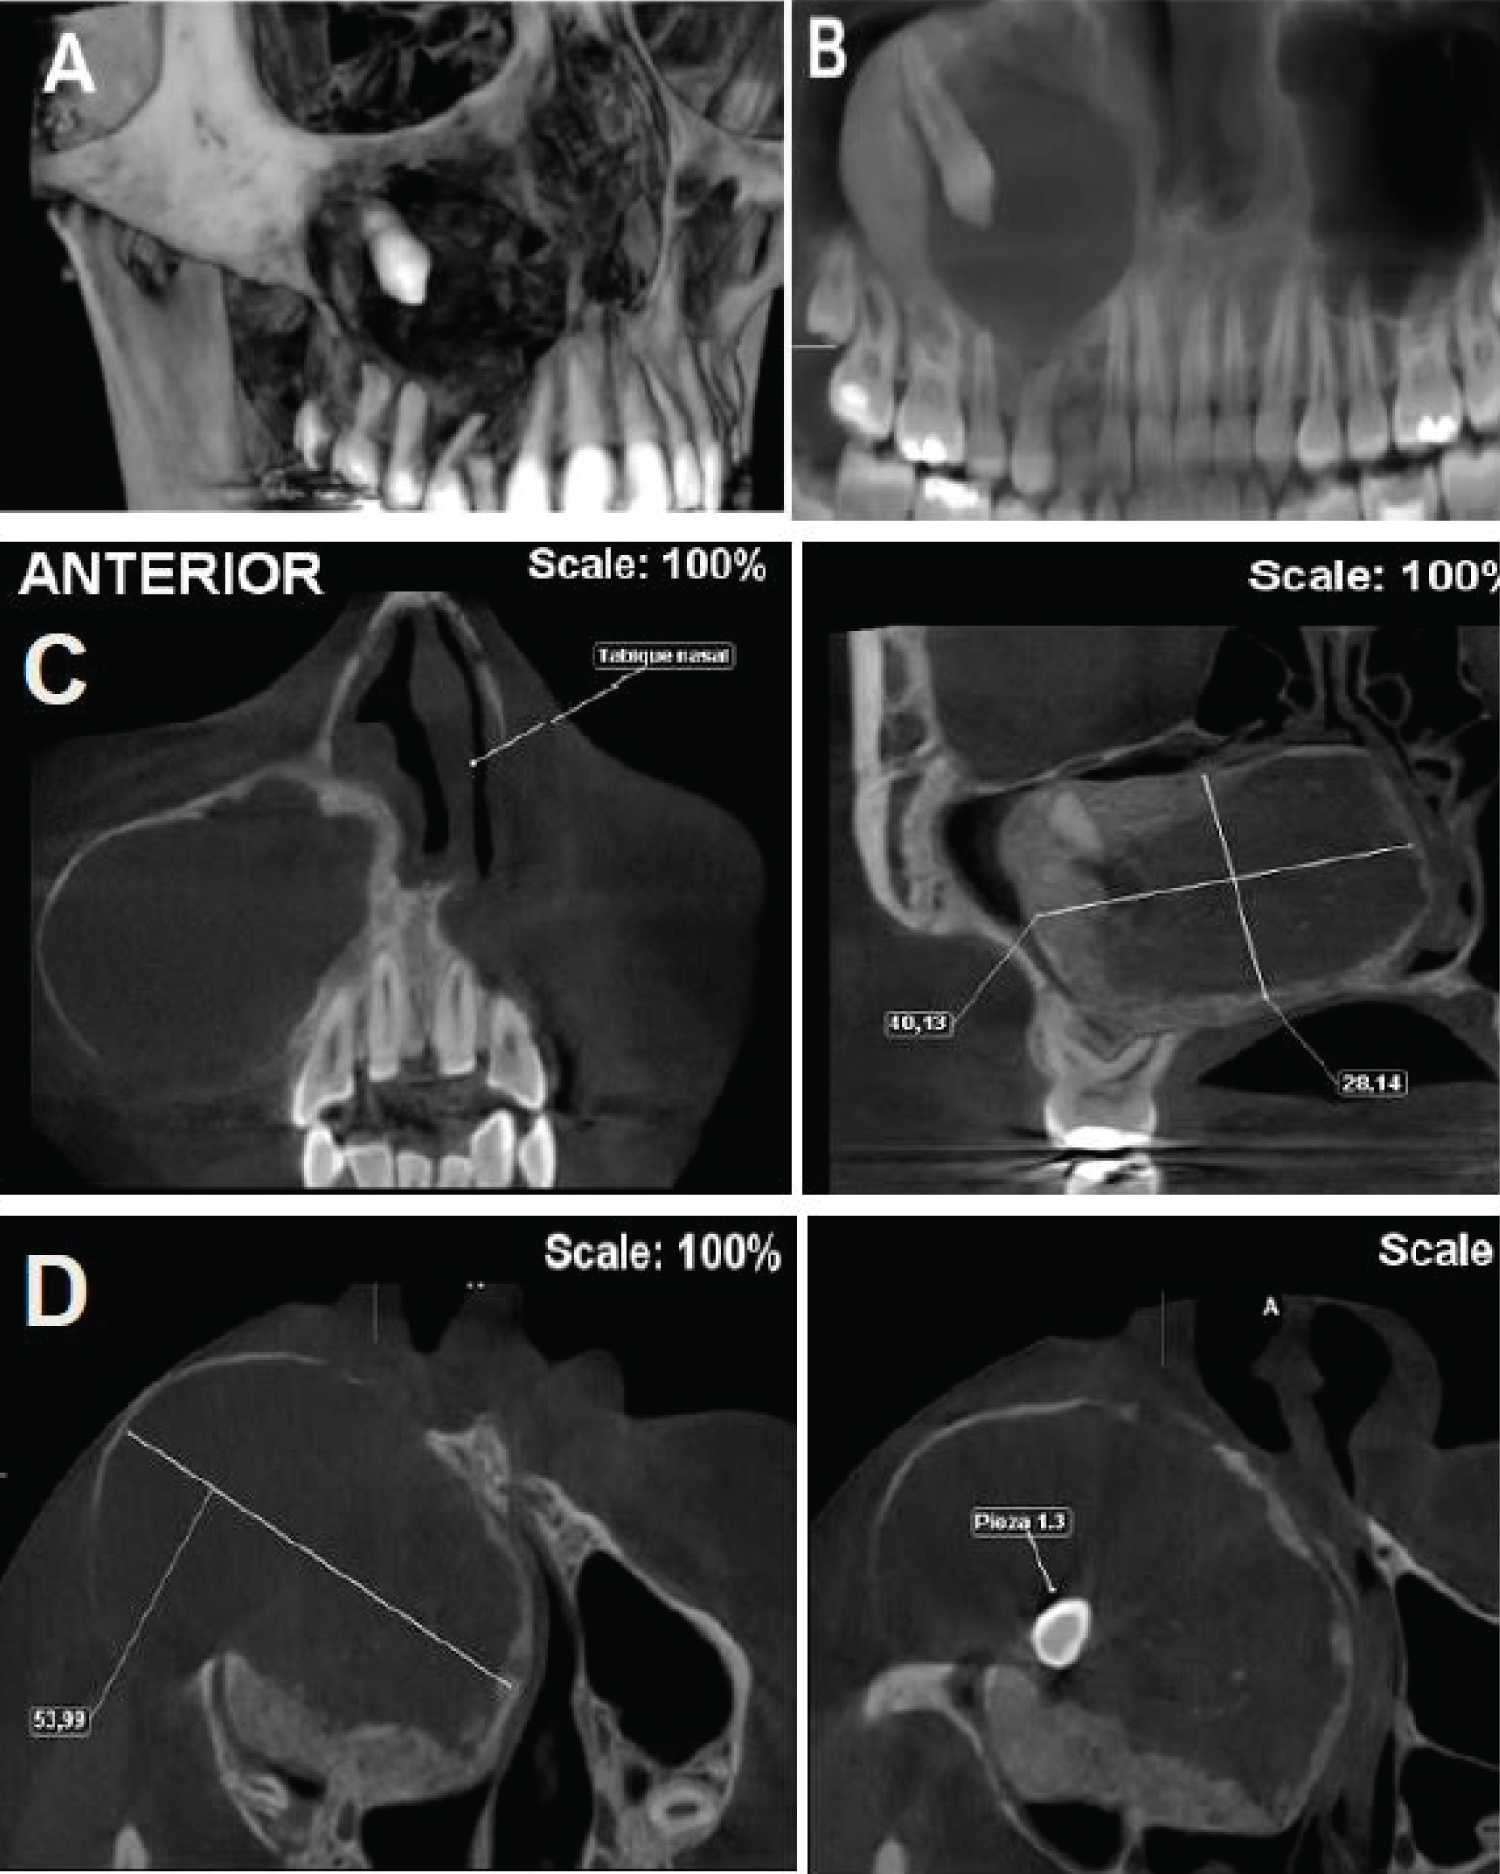

17-year-old female, with no diseases or allergies, attends evaluation with the Maxillofacial Surgery team at "Hospital del Carmen" (Santiago, Chile) for progressive right hemimaxillary volume increase. At the extraoral examination, the increase in volume was in the right genian region, causing facial asymmetry, with clear limits and hard on palpation. Intraoral examination revealed persistence of tooth 5.3 and clinical absence of tooth 1.3. Imaging tests were requested: Panoramic radiography and cone beam tomography where a tumor mass was visualized in relation to tooth 1.3 included in the posterosuperior wall of the right maxillary sinus, 5 cm in diameter, which displaces nasal and sinus mucosa (Figure 1). The condition is explained to the patient, and it is decided to excise the lesion, including an excisional biopsy in the procedure, plus the installation of a drain.

Figure 1: A) 3D reconstruction tumor mass; B) Orthopantomography pre surgical; C) Coronal cut and D) Axial cut. View Figure 1